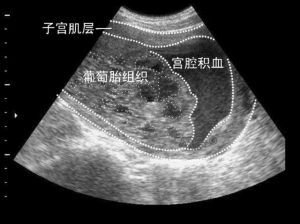

4.超聲檢查:觀察卵泡發育、排卵和黃體情況,並排除卵巢腫瘤。